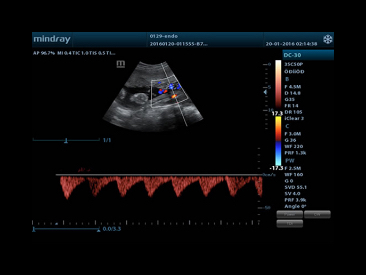

iTouchTM

Gain instant auto image optimization in B, Color and PW Modes on the click of a single key.